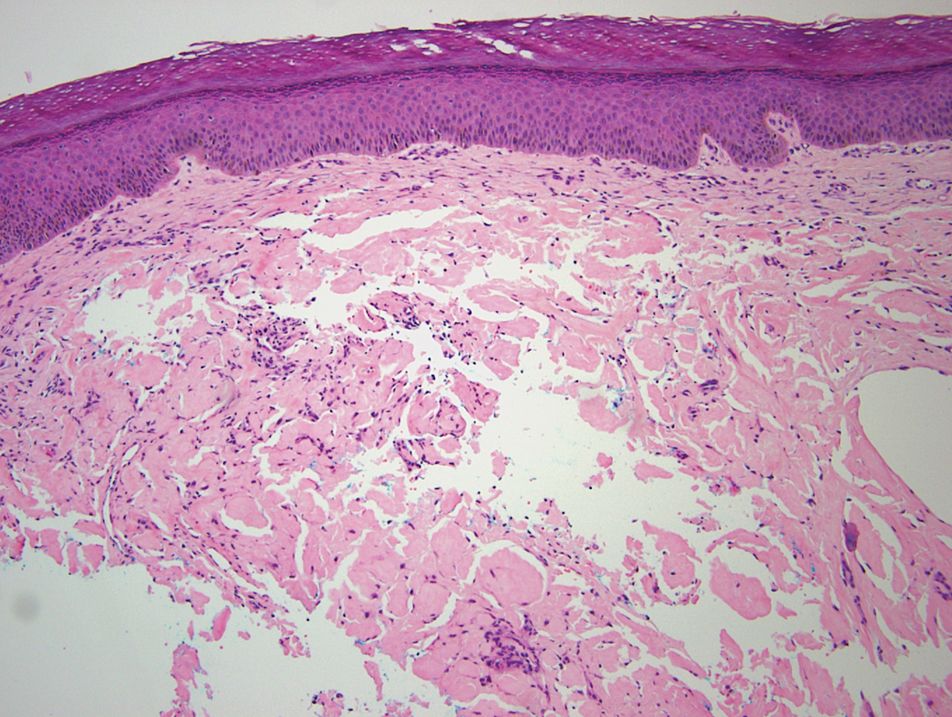

Relevant laboratory data included a fasting glucose level of 197 mg/dL and a glycohemoglobin of 9.3%. A biopsy of the lesion on the left lower abdomen revealed eosinophilic amorphous deposits with fissuring in the dermis (Figure 5). Congo red stain was positive with green birefringence under polarized light. Liquid chromatography–tandem mass spectrometry of the specimen showed deposition of AIns amyloid. The patient began injecting away from the amyloid nodules without development of any new lesions. The original nodules have persisted, and surgical excision is planned.

A majority of cases of iatrogenic amyloid have been described as single, firm, subcutaneous masses at an injection site that commonly are misdiagnosed as lipomas or lipohypertrophy.7-11 To our knowledge, none of the reported cases resembled the multiple, discrete, exophytic nodules seen in our patients.3,4 The surrounding hyperkeratosis noted in patient 1 is another uncommon feature of AIns amyloidosis (Figures 1 and 2). Only 3 AIns amyloidosis cases described lesions with acanthosis nigricans–like changes, only 1 of which provided a clinical image.6,7,12The mechanism for the acanthosis nigricans–like changes may have been due to the high levels of insulin at the injection site. It has been suggested that the activation of insulinlike growth factor receptor by insulin leads to the proliferation of keratinocytes and fibroblasts.6 Histologic examination of AIns amyloidosis lesions generally demonstrates deposition of homogenous eosinophilic material consistent with amyloid, as well as positive Congo red staining with green birefringence by polarization. Immunohistologic staining with insulin antibody with or without proteomic analysis of the amyloid deposits can confirm the diagnosis. In both of our patients’ specimens, liquid chromatography–tandem mass spectrometry was performed for proteomic analysis, and results were consistent with AIns amyloidosis.